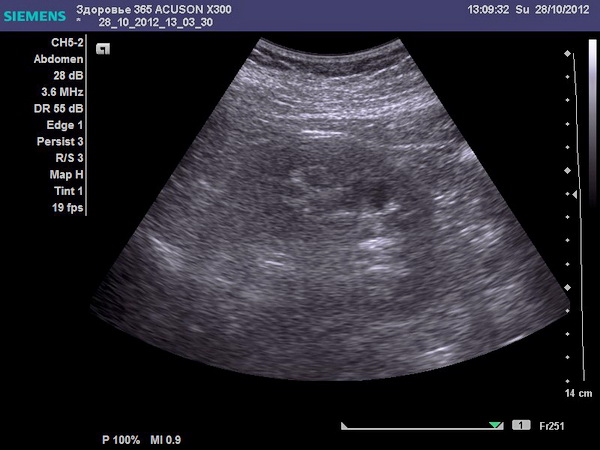

- УЗИ – показывает камни в почках и изменения органов малого таза, ЖКТ.

- УЗИ;

Ультразвуковое исследование